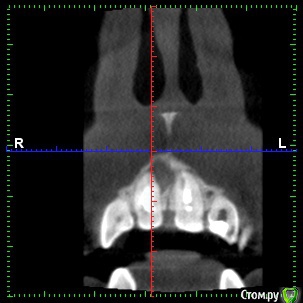

dentikl Опубликовано 22 декабря, 2016 Автор Поделиться Опубликовано 22 декабря, 2016 Потому что дефект 3-х стеночный и не выходит за границы контура челюсти,об'ем конечно кости уменьшаетсявот этот случай требует мембраны и индуктора?Ретроградно пломбировать даже если пройду на ревизии? Ссылка на комментарий

Доктор Добрых Дел Опубликовано 22 декабря, 2016 Поделиться Опубликовано 22 декабря, 2016 В области 11 случайно не трещина корня? Медиально очаг деструкции как-то намекает на это 1 Ссылка на комментарий

Тимур86 Опубликовано 22 декабря, 2016 Поделиться Опубликовано 22 декабря, 2016 киста сбоку говорит о том что в корне скорее всего трещина Ссылка на комментарий

Bier Опубликовано 22 декабря, 2016 Поделиться Опубликовано 22 декабря, 2016 не трещина там, а латераль скорее всего. Так высоко корень только от удара может сломаться. dentikl методика РВК применяется только при невозможности или безуспешности ортоградного лечения. Т.е. в вашем случае оперировать не нужно, нужно ждать излечения. Если же вы проводите РВК - единственным смыслом этой операции является установка апикальной пломбы, желательно не короче 3-4мм вглубь канала. Прорут, Триоксидент, IRM, или биокерамика - подходят для этих целей. 4 Ссылка на комментарий

dentikl Опубликовано 3 января, 2017 Автор Поделиться Опубликовано 3 января, 2017 В области 11 случайно не трещина корня? Медиально очаг деструкции как-то намекает на этоВы правы.Там таки была перфа не середине мщ поверхности корня.Кисту извлекли,перф прикрыли,жду. Ссылка на комментарий

dentikl Опубликовано 3 января, 2017 Автор Поделиться Опубликовано 3 января, 2017 киста сбоку говорит о том что в корне скорее всего трещинаДа,там была перфа,Вы-правы. Ссылка на комментарий